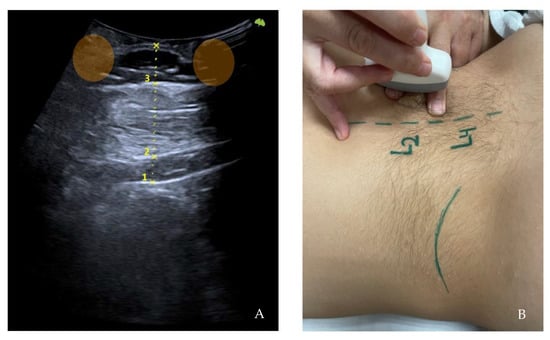

First, the last lumbar vertebra and the first sacral vertebra were located, and from there, the spinous processes of L4 and L2 were marked and assessed using ultrasonography. At the level of L2, the spinous process is located in the short axis, and the probe was moved to the right or left lateral side depending on randomization. We visualized the skin and the fatty tissue, we left the longissimus muscle towards the medial side, and we placed the iliocostalis lumborum muscle in the long axis, as well as the quadratus lumborum and the kidney, in the center of the screen. We asked the subjects to breathe in to see how the kidney descended and became more visible. When in maximum inspiration, we froze the image to make the following measurements: skin-upper edge of the iliocostalis lumborum muscle, skin-lower edge of the iliocostalis lumborum muscle, and skin-kidney. Then, a different researcher placed two fingers exerting pressure, as if it were the “tissue depression prior to performing the DP”. More ultrasound gel was placed between the fingers, and the sonographer placed the probe again in the short axis. An inspiration was requested to freeze the image and perform the same measurements mentioned above. At L4 level, the same protocol was followed with the difference in that, instead of performing the last skin-kidney measurement, the skin-peritoneum measurement was performed. The measurements were made on the right and left sides and with and without compression (Figure 3, Figure 4 and Figure 5).

Figure 3. Ultrasonography image. Short-axis measurements in L2 level, left side at rest. Skin-kidney (1), skin-iliocostalis lumborum bottom edge (2), and skin-iliocostalis lumborum top edge (3).